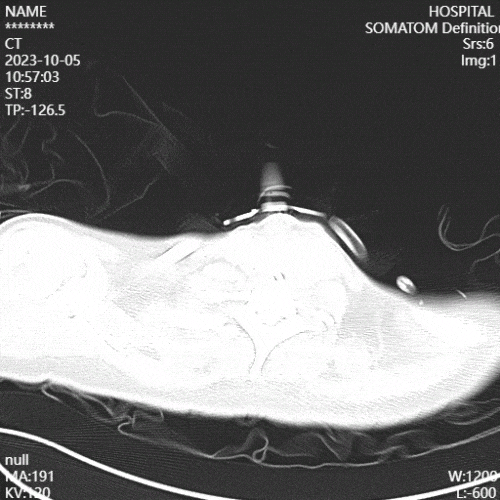

(5)康复措施及效果:复查影像学可见患者肺部炎性病变较前减少。

图片